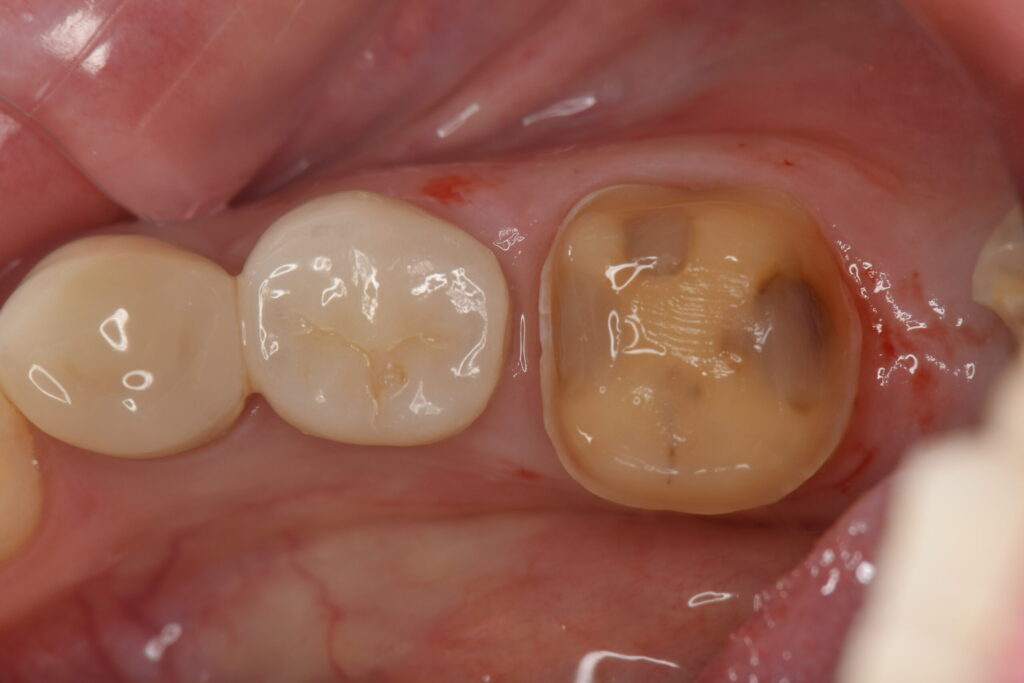

患者様はお久しぶりの歯医者さんとのこと、虫歯があると思うので良い治療でしっかり治していきたいとのことでしたので、虫歯再発率の低い自由診療を中心に治療内容とメリットデメリットについて説明を行いました。

患者様は精密治療を希望されたため、まずは左下の虫歯をジルコニアセラミックで被せ直しました。